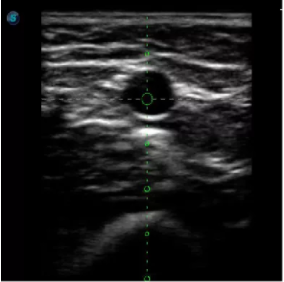

傳統(tǒng)腔內(nèi)探頭采用直柄設(shè)計(jì),在搭配穿刺架使用時(shí),手術(shù)空間小,不易操作;生殖專用的曲柄探頭,探頭柄采用彎曲成角度設(shè)計(jì),可實(shí)現(xiàn)監(jiān)視、取卵兩不誤,搭載穿刺架時(shí),可以清晰顯示穿刺針的進(jìn)針過程、深度和位置,實(shí)時(shí)監(jiān)視取卵全過程,保障取卵操作精準(zhǔn)與安全。

取卵臨床圖